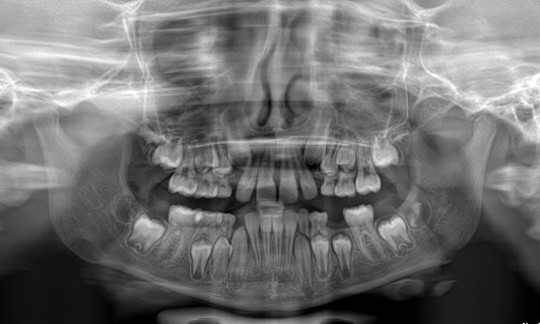

Most often X - ray is OPG (OrthoPantomoGram) frame that is made by extraoral imaging technique. It is the only imaging method, which is able to depict both jaws in the picture with the associated cavities, teeth, and both jaw joints.

+

Fig. 6. OPG